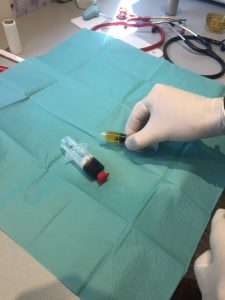

Gerben M. van Buul a étudié l’effet des concentrés plaquettaires sur des cultures de chondrocytes (cellules cartilagineuses) humains issus de genoux arthrosiques. De nombreuses études ont montré les effets anabolisants (càd permettant le développement) du PRP sur le chondrocyte sain. Tout l’intérêt de cette étude est d’analyser l’effet du PRP sur le cartilage dégénératif. La mise en évidence d’une inhibition des processus inflammatoires encourage son utilisation dans l ‘arthrose.

E. Anitua a observé l’effet du concentré plaquettaire sur des chondrocytes issus d’articulations arthrosiques. Il a mis en évidence un rôle stimulateur sur la sécrétion d’acide hyaluronique et la vascularisation

L’utilisation des concentrés plaquettaires dans l’arthrose et les chondropathies intéresse de nombreux auteurs, cherchant à préciser leur mode d’action et à comparer leur efficacité par rapport aux injections d’acide hyaluronique (AH) ou au placebo.

Elizaveta Kon a analysé l’efficacité d’un traitement par PRP versus acide hyaluronique dans le genou atteint d’arthrose ou de chondropathie dégénérative. Le protocole retenu consistait en l’injection de 5 ml de concentré 3 fois à 14 jours d’intervalle. Les patients ont été évalués avant traitement, à 2 mois et à 6 mois. Les résultats montrent une efficacité plus grande et plus prolongée du traitement par PRP chez les patients plus actifs et avec des lésions moins évoluées. Les résultats à 6 mois du traitement par PRP ou AH sont comparables chez les sujets plus âgés.

M. Bouvard et B. Eichene ont fait une revue de la littérature sur le sujet, ils ont retenus 6 études de haut niveau de preuve sur la chondropathie, 5 contre AH et 1 contre placebo. L’efficacité des PRP est supérieure aux AH ou au placebo, surtout chez les patients souffrant d’une chondropathie légère.

De plus en en plus de publications scientifiques concluent à une action des PRP supérieure ou égale à celle de l’acide hyaluronique, notamment pour les arthroses du genou débutantes, légères et modérées :

= le PRP présente donc un intêrêt majeur dans le traitement de l’arthrose, notamment du genou ++, et plutôt sur les arthroses débutantes.